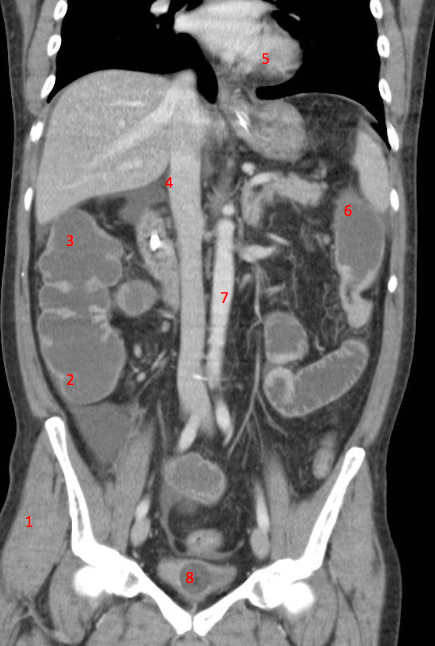

Number 1?

R Kidney

Number 2?

IVC

Number 4?

Rt lobe liver

R lung

Rt lobe of liver

Number 8?

Bladder